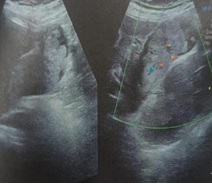

Case Presentation: A 48-year-old female presented with complaints of vague upper abdominal pain for last 10 days.Ultrasound abdomen revealed polypoidal mass filling gall bladder lumen measuring 7x3.8 cm. MRCP revealed hypointense mass lesion within gallbladder lumen with its stalk at the hepatic surface of gall bladder. CT abdomen revealed heterogeneously enhancing gall bladder mass with no regional lymphadenopathy. Serum tumor markers of CEA, CA19.9 were normal. Patient underwent en bloc resection of 2 cm segment IVB liver along with gallbladder. Intraoperative frozen section specimen revealed exophytic polypoidal papillary lesion in distal body of gallbladder measuring 5x4x3 cm. Microscopic features revealed intracholecystic papillary neoplasia with low-grade dysplasia. Regional lymphadenectomy was not performed. Final diagnosis of Intracholecystic papillary neoplasm,gastric type was confirmed and patient was kept on close follow up.